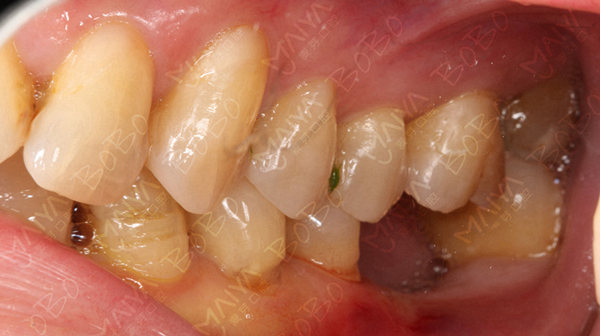

医生为赵阿姨检查牙齿情况

赵阿姨牙齿缺失情况